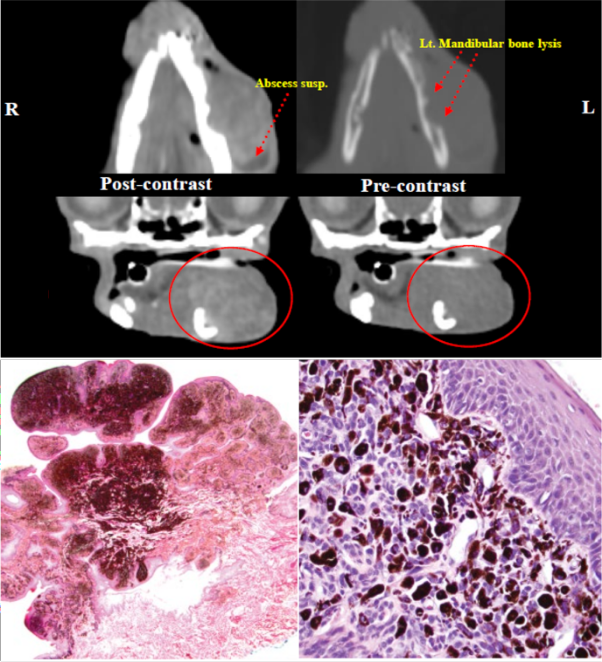

먼저, 방사선, 초음파, 컴퓨터 단층촬영(CT) 등의 영상검사를 통해 종양의 크기 및 침습 범위와 전이 여부를 평가한 다음, 원발 종양과 함께 림프절 등 전이가 의심되는 조직의 전체 또는 일부를 수술적으로 절제하여 조직병리검사를 진행합니다.

CT(위) 및 조직병리검사(아래)상에서 확인되는 구강 흑색종의 모습 (사진=Tumors in Domestic Animals, 5th ed)